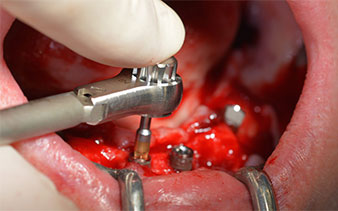

Il protocollo chirurgico per il sistema di implantologia utilizzato (SKY, Bredent medical) prevede una velocità di 1.200 giri/min per la perforazione pilota (Fig. 7 - 9).

Questa è la prossima posizione programmata nel sistema Implantmed. Qui è possibile vedere il contrangolo W&H impugnato a un angolo di 45 gradi in posizione medio-caudale, nella zona del 45, al fine di salvaguardare il nervo mentoniero. Il forame mentoniero è un punto di riferimento anatomico per tutte le perforazioni in quest'area. I fori successivi sono realizzati con una velocità ridotta, pari a 300 giri/min (Fig. 10 e 11).